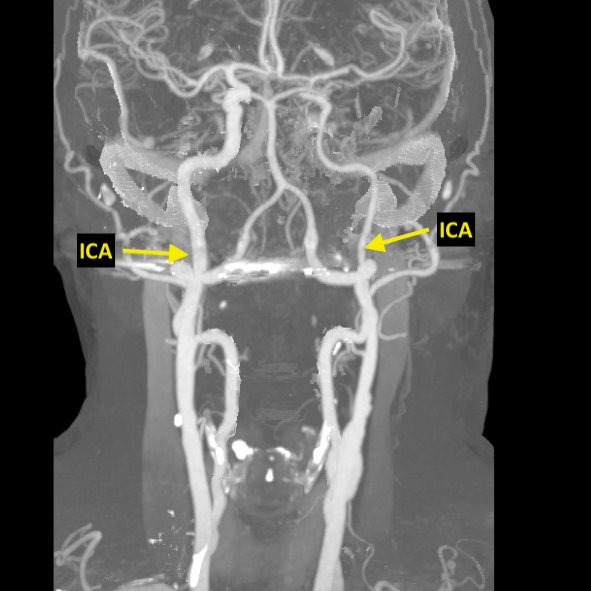

Criteria 1: Reduction of the distal ipsilateral ICA diameter in comparison to the contralateral ICA (as seen on their CTA)